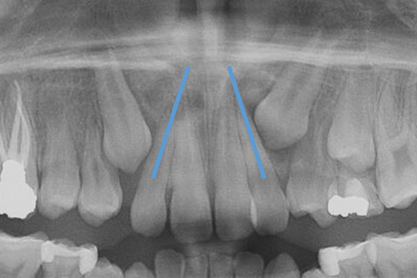

Dental impactions may occur for several reasons. A common occurrence is insufficient arch length leading to crowding. Another potential reason is early loss of primary teeth without proper space maintenance, allowing the permanent dentition to drift mesially and block out the primary tooth's successor. Maxillary canines are the most commonly impacted teeth besides third molars. These teeth have the longest path of eruption, are one of the last teeth to erupt into the mouth, easily become blocked out due to crowding or trauma history, and have a genetic component to being palatally impacted.5,6 Early signs of canine impaction may be severe crowding and the permanent lateral incisor crowns flaring distally. The crown of the impacted canine, in essence, is applying pressure to the roots of the lateral incisors in these instances (Figure 3 and Figure 4).

Fig 3. Impacted canine, dentofacial signs.

Figure 3

Fig 4. Impacted canine, radiographic signs. Lateral incisor crown distal flaring is apparent.

Figure 4